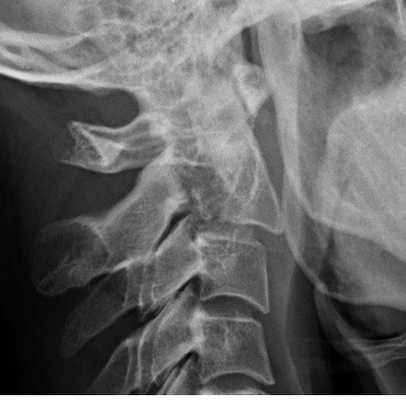

Пациент молодой человек 1992г.р., получил травму вследствие падения с высоты около 3 метров. Почувствовал резкую боль в шейном отделе позвоночника. Был доставлен в ближайшую больницу, где выполнена рентгенография шейного отдела позвоночника и выявлена переломо - вывих в атланто - аксиальном сочленении, перелом зубовидного отростка (РИС 1). С целью дообследования и нейрохирургического лечения пациент переведен в нашу клинику. Состояние при поступлении: Общее состояние удовлетворительное. Кожа чистая, обычной окраски. Отеков нет. Над легкими везикулярное дыхание, хрипов нет. Тоны сердца ясные, ритм правильный. АД 130/70 мм рт. ст. ЧСС - 76 в минуту. Живот при пальпации мягкий, безболезненный во всех отделах. Неврологический статус: В сознании, контактен, адекватен. Менингиальной симптоматики нет. Движения глаз в полном объёме. Зрачки по средней линии, равновеликие, фотореакция живая. Лицо симметричное. Чувствительность на лице не изменена. Глотание, фонация сохранены. Язык по средней линии. Пальценосовую пробу выполняет удовлетворительно с двух сторон. Тазовые функции контролирует. Движения в шейном отделе позвоночника ограничены, болезненны. Сухожильные рефлексы D=S.

Рентгенограмма. Подвывих в шейном отделе позвоночника. Цветовая обработка изображения.

Перелом С2. Рентгенограмма в боковой проекции. Кольцо незамкнуто вследствие смещения зубовидного отростка назад.

Перелом С2 «повешенного». Рентгенограмма в боковой проекции. Смещение тела С2 вперед, отрыв задних элементов.

Обследование начинается со стандартной рентгенографии в 3 проекциях - боковой, передне-задней (прямой) и через рот.